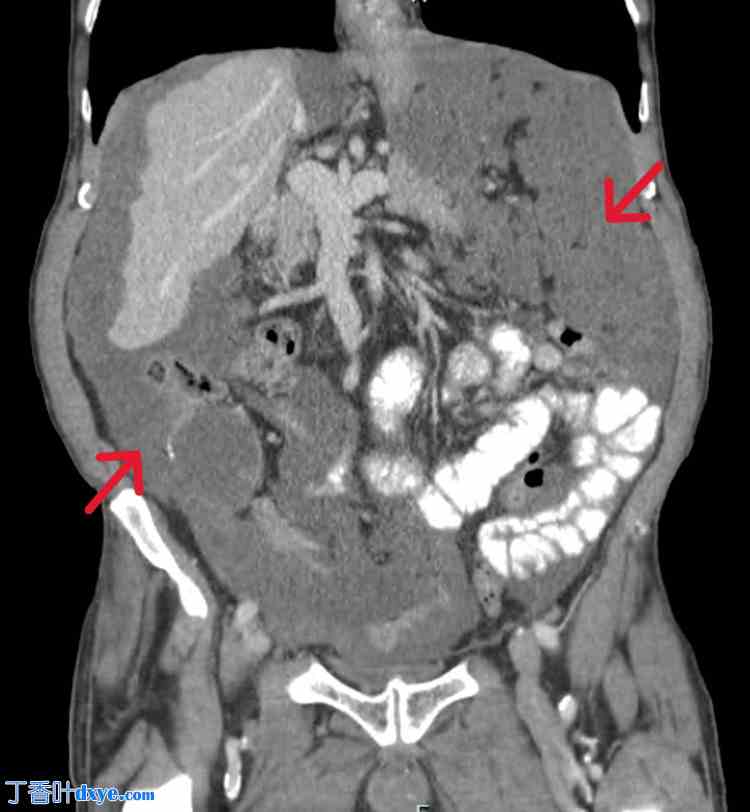

图1. 腹部CT(冠状面)。

红色箭头指向压迫所有主要腹膜内器官的肿块。